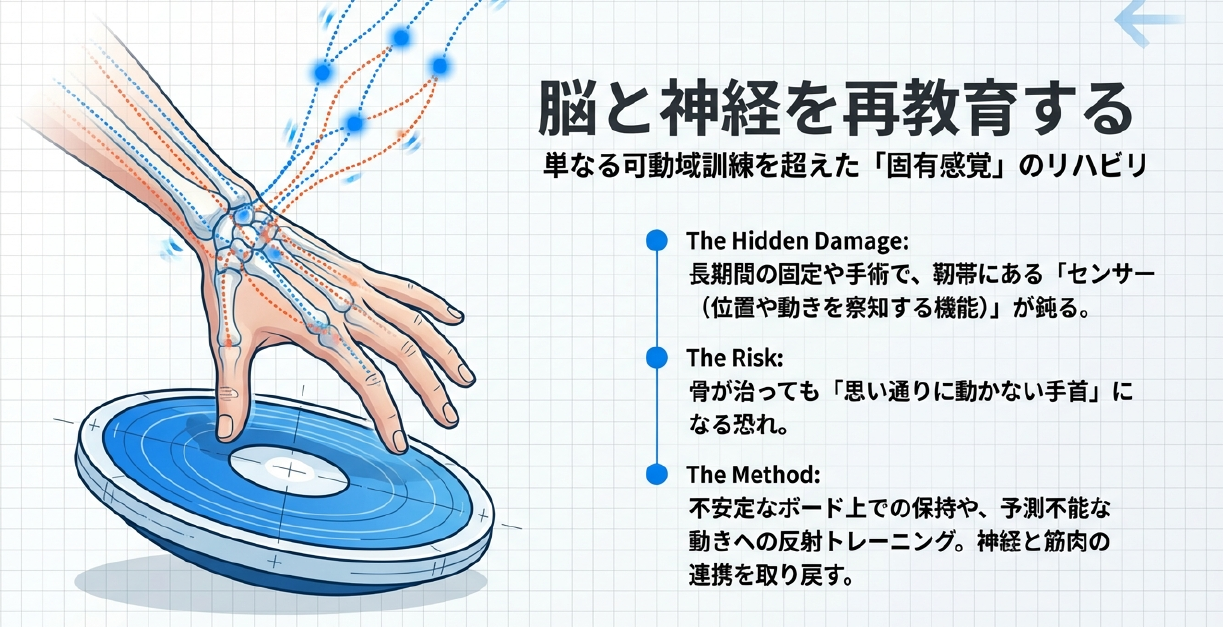

さらに、スポーツへの復帰という観点では、単に骨がつながったかどうかだけでなく、手首の「固有感覚(プロプリオセプション)」の再教育が重要視されています。舟状骨周囲の靭帯には、手首の位置や動きを察知するセンサーが密集しています。長期間の固定や手術によってこのセンサーが鈍ると、骨は治っても「思い通りに動かない手首」になってしまいます。そのため、最新のリハビリプログラムでは、不安定なボードの上で手をつく練習や、予測不能な動きに対する反射トレーニングなど、神経・筋肉の連携を重視したアプローチが取り入れられています。